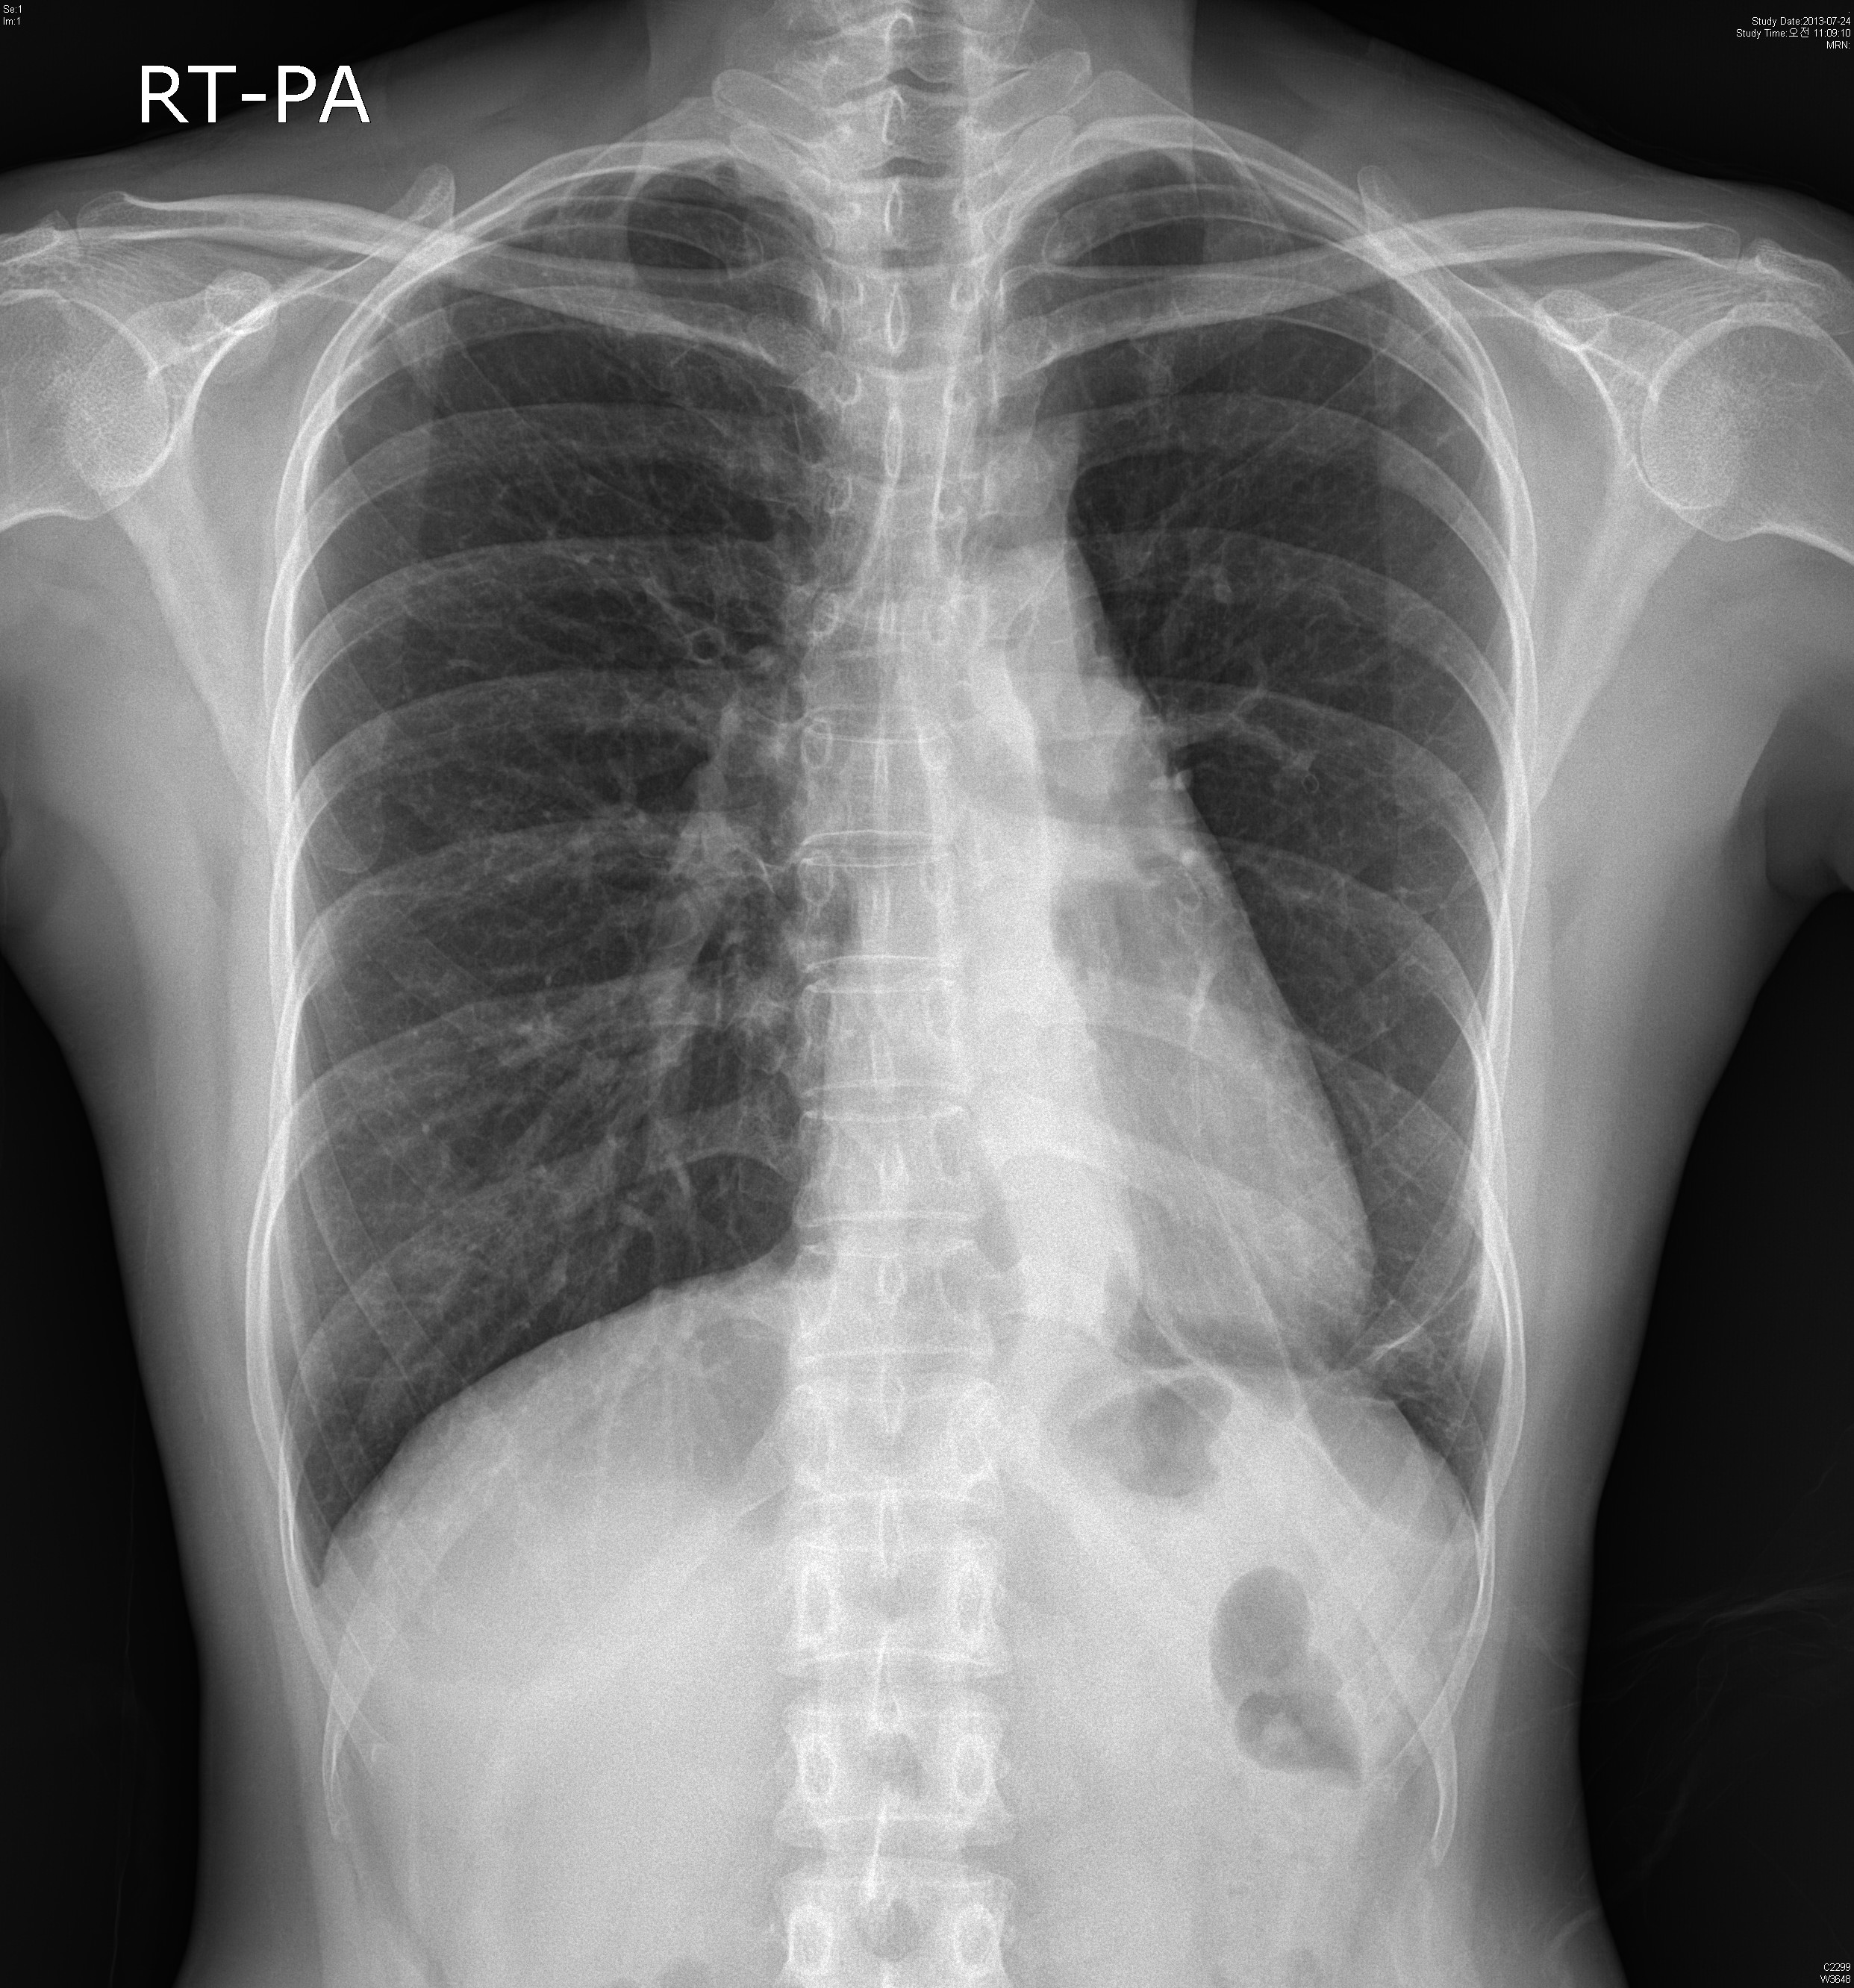

45¼¼ ¿©ÀÚ. chronic coughÀÖ´ø ºÐÀ¸·Î hemoptysis·Î ¿Ü·¡ ³»¿ø.

CXR»ó °üÂûµÇ´Â ¼Ò°ß ȤÀº º´¸í ´äº¯ÁÖ¼¼¿ä.